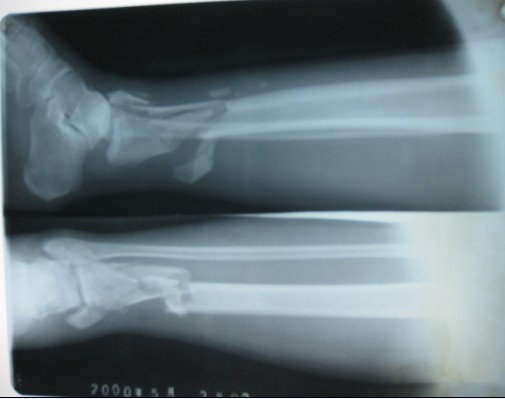

胫骨骨不连骨瓣游离移植修复术